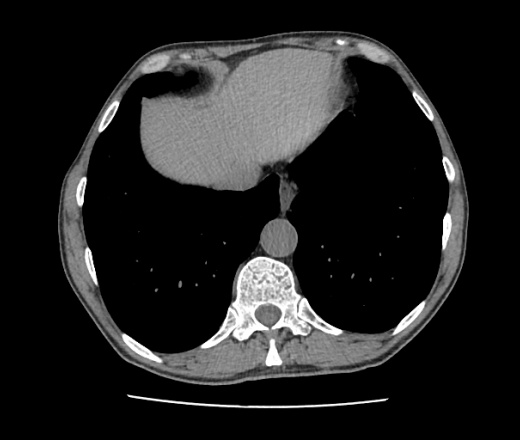

2 кт подряд

2 кт подряд 111 фото